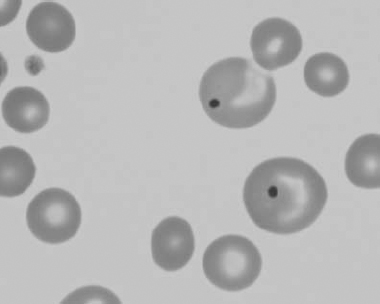

Figure 1.10 Canine blood film showing echinocytes I (also see color section).

Figure 1.11 Canine blood film showing echinocytes III (also see color section).